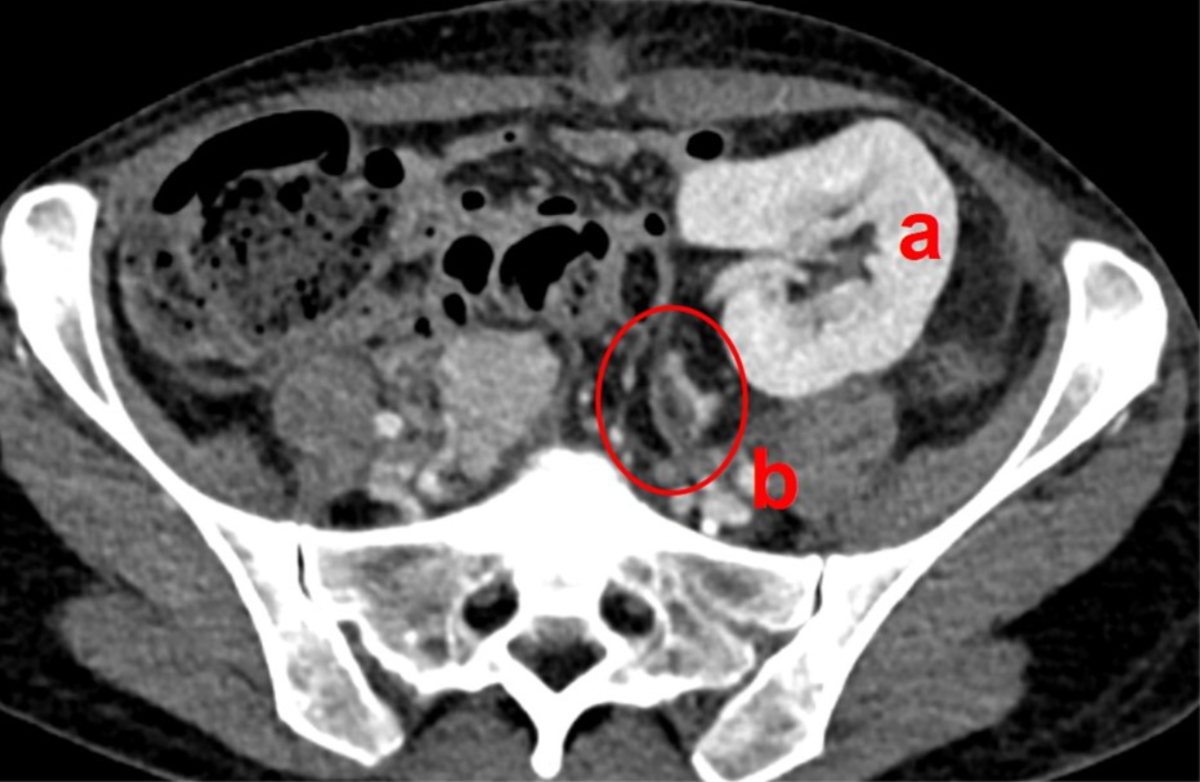

However, due to repeated episodes of diarrhoea and inflammation, the patient’s cortisol turnover was elevated and the replacement therapy had to be continued, and later even increased. Therefore, ACTH levels remained below the minimum at two and three months after transplantation. Aldosterone levels remained low as well. The patient was discharged with a daily dosage of 50 mg hydrocortisone and 0.1 mg fludrocortisone. Repeated contrast-enhanced CT scans confirmed regular perfusion of the adrenal graft (figure 2).

Figure 2Adrenal graft perfusion. Computed tomography on postoperative day 8 shows regular perfusion of the kidney (a) and adrenal graft (b, encircled).